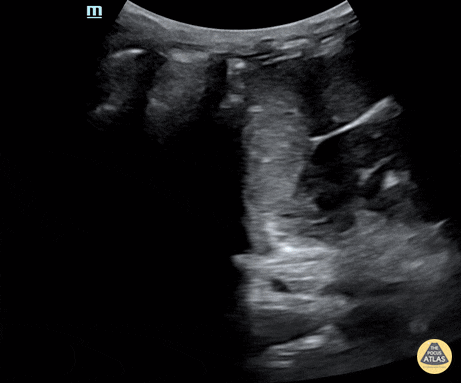

Normal LUQ on Efast of a 21-month-old. Contributor: Jaron Smith, MD, Phoenix Children's Hospital

View: Unspecified Parasternal Long Axis Parasternal Short Axis Apical Four-Chamber Subcostal Four-Chamber Subcostal Inferior Vena Cava Right Upper Quadrant Left Upper Quadrant Suprapubic Longitudinal Suprapubic Transverse Subxiphoid Anterior Thoracic Phrenic